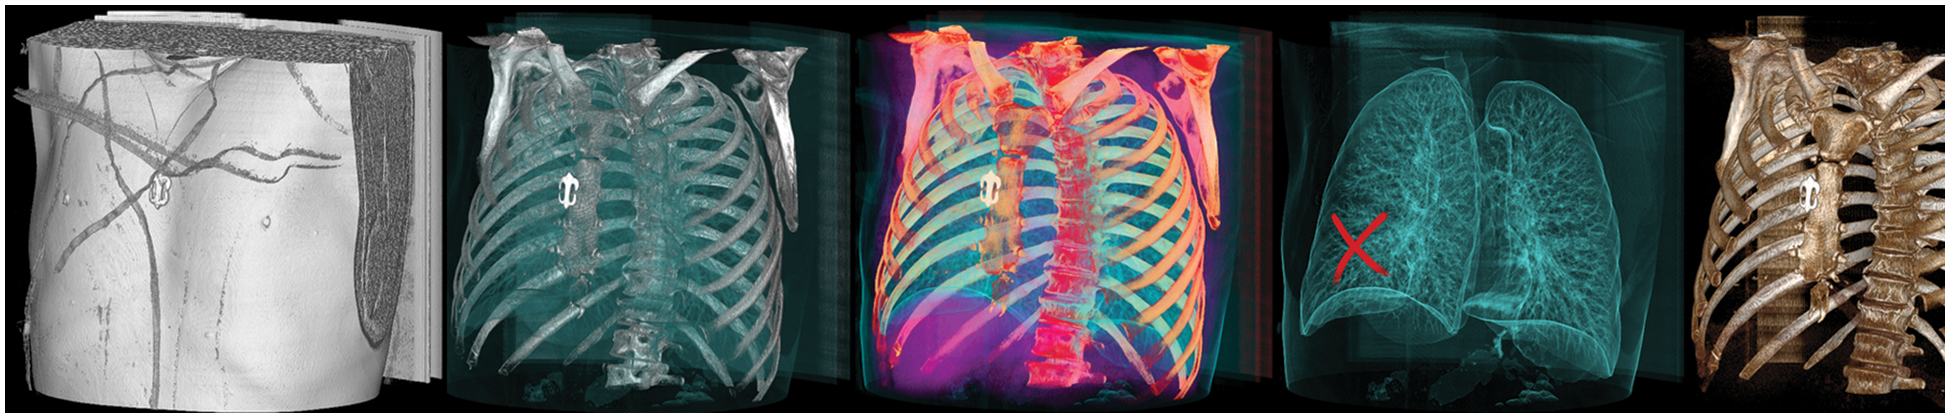

The research study attempted to detect real cancer samples from deep fake images to improve the classification performance. The type of data required for the project was a dataset consisting of tampered and untampered medical deep fake images. To obtain sufficient data, the proposed research study chose this dataset [22], which includes deep fakes in CT scans of human lungs that were tampered with to remove real cancer and inject fake cancer. A preview of the dataset can be seen in Fig. 10.

Figure 10: Sample images from the dataset